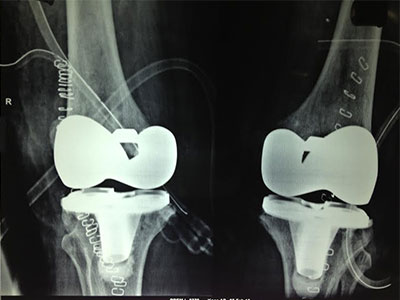

Total Knee Replacement is a procedure in which the parts of the bones that rub together are resurfaced with metal and plastic implants. Precision instruments are used to remove and replace damaged parts of the bone with implants. The surface of the femur is replaced with a rounded metal component that matches closely the curve of your natural bone. And the surface of the tibia/leg bone is substituted with a smooth plastic component.

Bone cement is used to secure the knee implants.

Partial knee replacement surgery removes damaged tissue and bone in the knee joint. The damaged areas are replaced with a man-made implant, called a prosthetic.

- A man-made part made of plastic and metal is placed into the knee.

- Once the part is in the proper place, it is attached with bone cement.